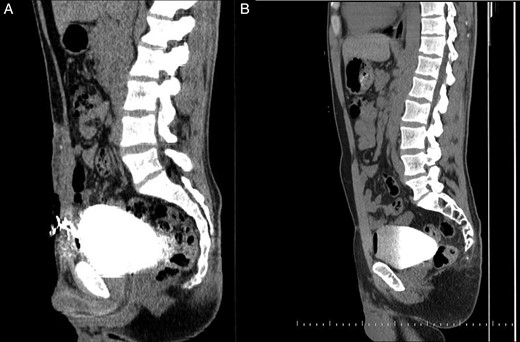

A 32-year-old male presented to our outpatient clinic with complaints of dysuria and continuous leakage of urine from the fistula tract located at the midpoint of the symphysis pubis and the umbilicus for a long time. In his medical history, he underwent open surgery due to a large bladder stone at 24 years of age. A nontender mass was palpable around the orifice on physical examination. The urinalysis revealed pyuria and microscopic hematuria, but the urine culture was sterile. An abdominal ultrasonography was done, but no remarkable pathology was reported. A computerized tomography (CT) cystogram demonstrated an aberrant connection between the anterior bladder wall and the external surface of the skin (Fig. 1A). Subsequently, under general anesthesia, patient was placed in a low lithotomy position. Cystoscopy was performed to visualize and cannulate the fistula tract with a 6-Fr ureteral catheter. A midline infraumblical incision was made involving the circumscribing incision around the fistula. The fistula tract was identified until the bladder with blunt dissection. After excision of fistula tract with wide perivesical tissue debridement, a peritoneal cavity was opened and an omental V-shaped flap was prepared (Fig. 2A). An omental flap was based on a more reliable right gastroepiploic artery and brought down to the surgical field and placed upon the anterior bladder wall. The omental flap was sutured and quilted on the bed of the anterior bladder wall with the interrupted 2-0 polyglactin sutures (Fig. 2B). The border of the suture lines included from the bladder neck to the posterior bladder wall and up to endopelvic fascia at the lateral sides. A closed pelvic drain was also placed. No intraoperative and postoperative complications were noted. The drain was removed day after surgery, and the patient was discharged at the postoperative day 2. A Foley catheter was removed at the postoperative day 21 after a CT cystogram revealed no leakage from the bladder (Fig. 1B). At the last follow-up visit, patient was relieved of all his complaints.

(A) A CT cystogram demonstrates an aberrant connection between the anterior bladder wall and the external surface of the skin. (B) A CT cystogram shows no leakage from the bladder on postoperative day 21.